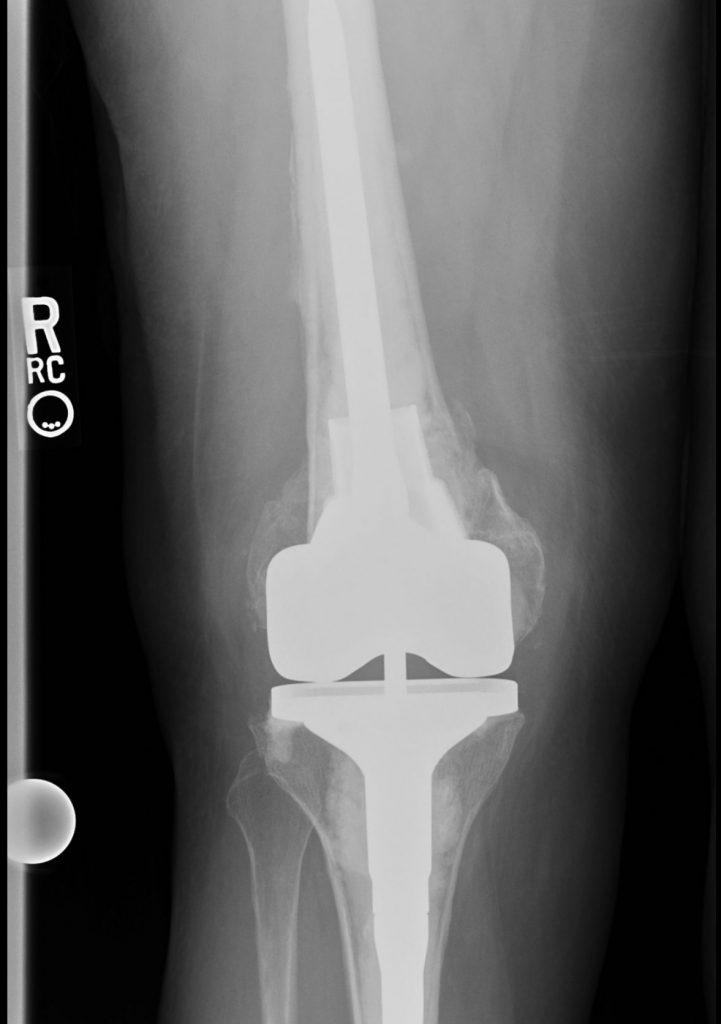

Over a year ago, I tripped and broke the base of my femur, requiring emergency surgery with plates and bolts to repair and set my leg. I was non-weight bearing for 10 weeks progressing to full weight bearing over several months. Seven months in my recovery, my kneecap dislocated by simply rolling over in bed, sending me to the hospital for sedated manipulation back into place. It happened two more times with ER visits, requiring me to wear a kneecap immobilizer 24/7. With this complication, CT scans were done which showed that my femur grew back at an angle and rotated which caused my lower let to jut out to the right. My kneecap had no channel to sit, forcing me to wear an immobilizer 24/7. Because my legs were deformed, walking short distances were difficult. The plan was to perform a distal femur replacement (removing the base of my femur) and a hinged knee replacement (last resort). I was referred to Dr. Gausden at HSS and after meeting her at my pre-op appt, she said I was too young to loosen the base of my femur and she would do her best to save my femur. With mere determination and over 6 hours of surgery, Dr. Gausden saved my femur and performed a total knee replacement. She was a miracle worker. I had the best experience at HSS with Dr. Gausden and her team. I can't thank Dr. Gausden enough for her skillset and determination to save my femur.